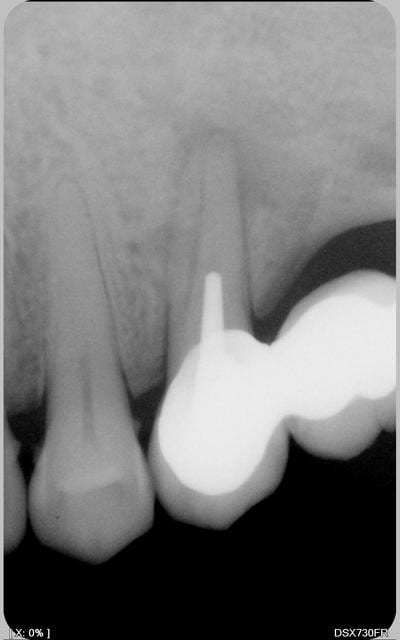

la radio.pas de poche paro

heu... tu nous a remis la même radio...

Tu peux nous donner la radio post endo?

Tu as bien du avoir au moins deux canaux, non?

radio

reradio